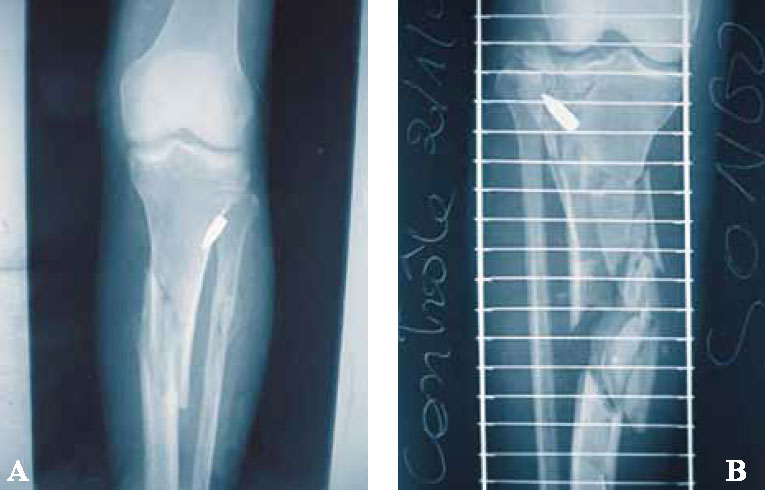

Если инородное тело давит на нерв и причиняет острую боль или парестезию (рисунок 11). Так же, как и в предыдущем случае, извлечение производят в ходе плановой операции.

Рисунок 11. A) Пуля в переднелатеральном отделе голени надавливает на общий малоберцовый нерв. B) Пуля не контактирует с нервом